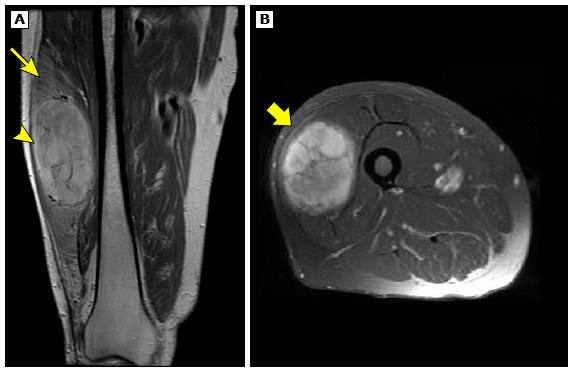

При проведении МРТ используются радиоволны и мощные магниты для получения снимков областей внутри тела. МРТ является предпочтительным исследованием при саркоме мягких тканей туловища, конечностей, головы и шеи. Этот метод позволяет оценить изображение в разных плоскостях, а значит, точнее определить размер опухоли и ее связь с окружающими тканями.

Признаки, указывающие на злокачественность:

• неоднородная структура опухоли;

• наличие некроза (зоны мертвых тканей опухоли);

• отек вокруг опухоли и накопление контраста в ее тканях;

• инфильтративный рост (прорастание в окружающие ткани).

МРТ мягкотканной саркомы бедра. Источник изображения: UpToDate, “Clinical presentation, diagnostic evaluation, and staging of soft tissue sarcoma”